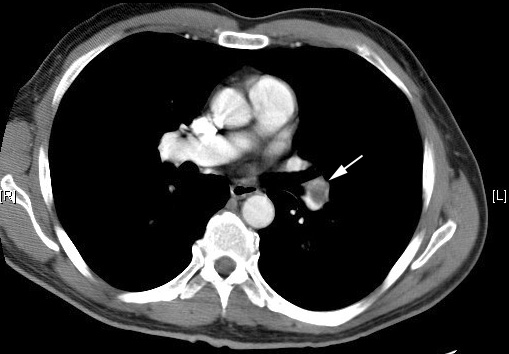

How To Read A CT Pulmonary Angiogram Part II: How ... - YouTube

How to diagnose a pulmonary embolism. A step by step description of the findings of two patients with positive findings on CT Pulmonary Angiogram (CTPA or PE Study). by Sarel Gaur MD PGY3 Radiology, SUNY Stony Brook Hospital ... View Video

CT: Diagnosis Of Pulmonary Embolism - Chest X-Ray

1 CT: Diagnosis of Pulmonary Embolism Jud W Gurney MD FACR University of Nebraska Medical Center The movie Hunt for Red October is about about a silent ... Get Doc